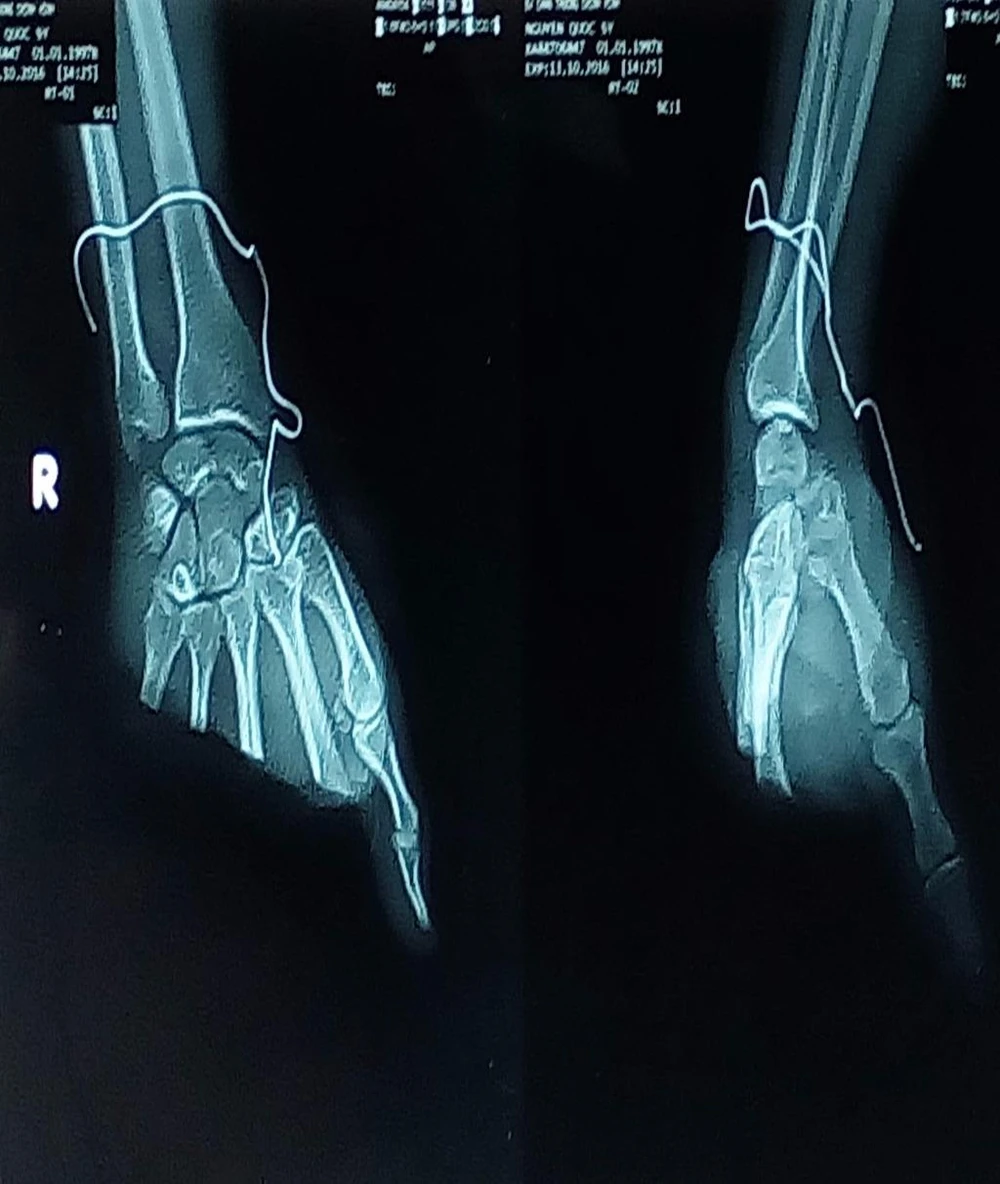

chụp phim

Kết quả chụp X quang cho thấy bàn tay phải bệnh nhân bị đứt lìa. Ảnh: HÒA KHÁNH